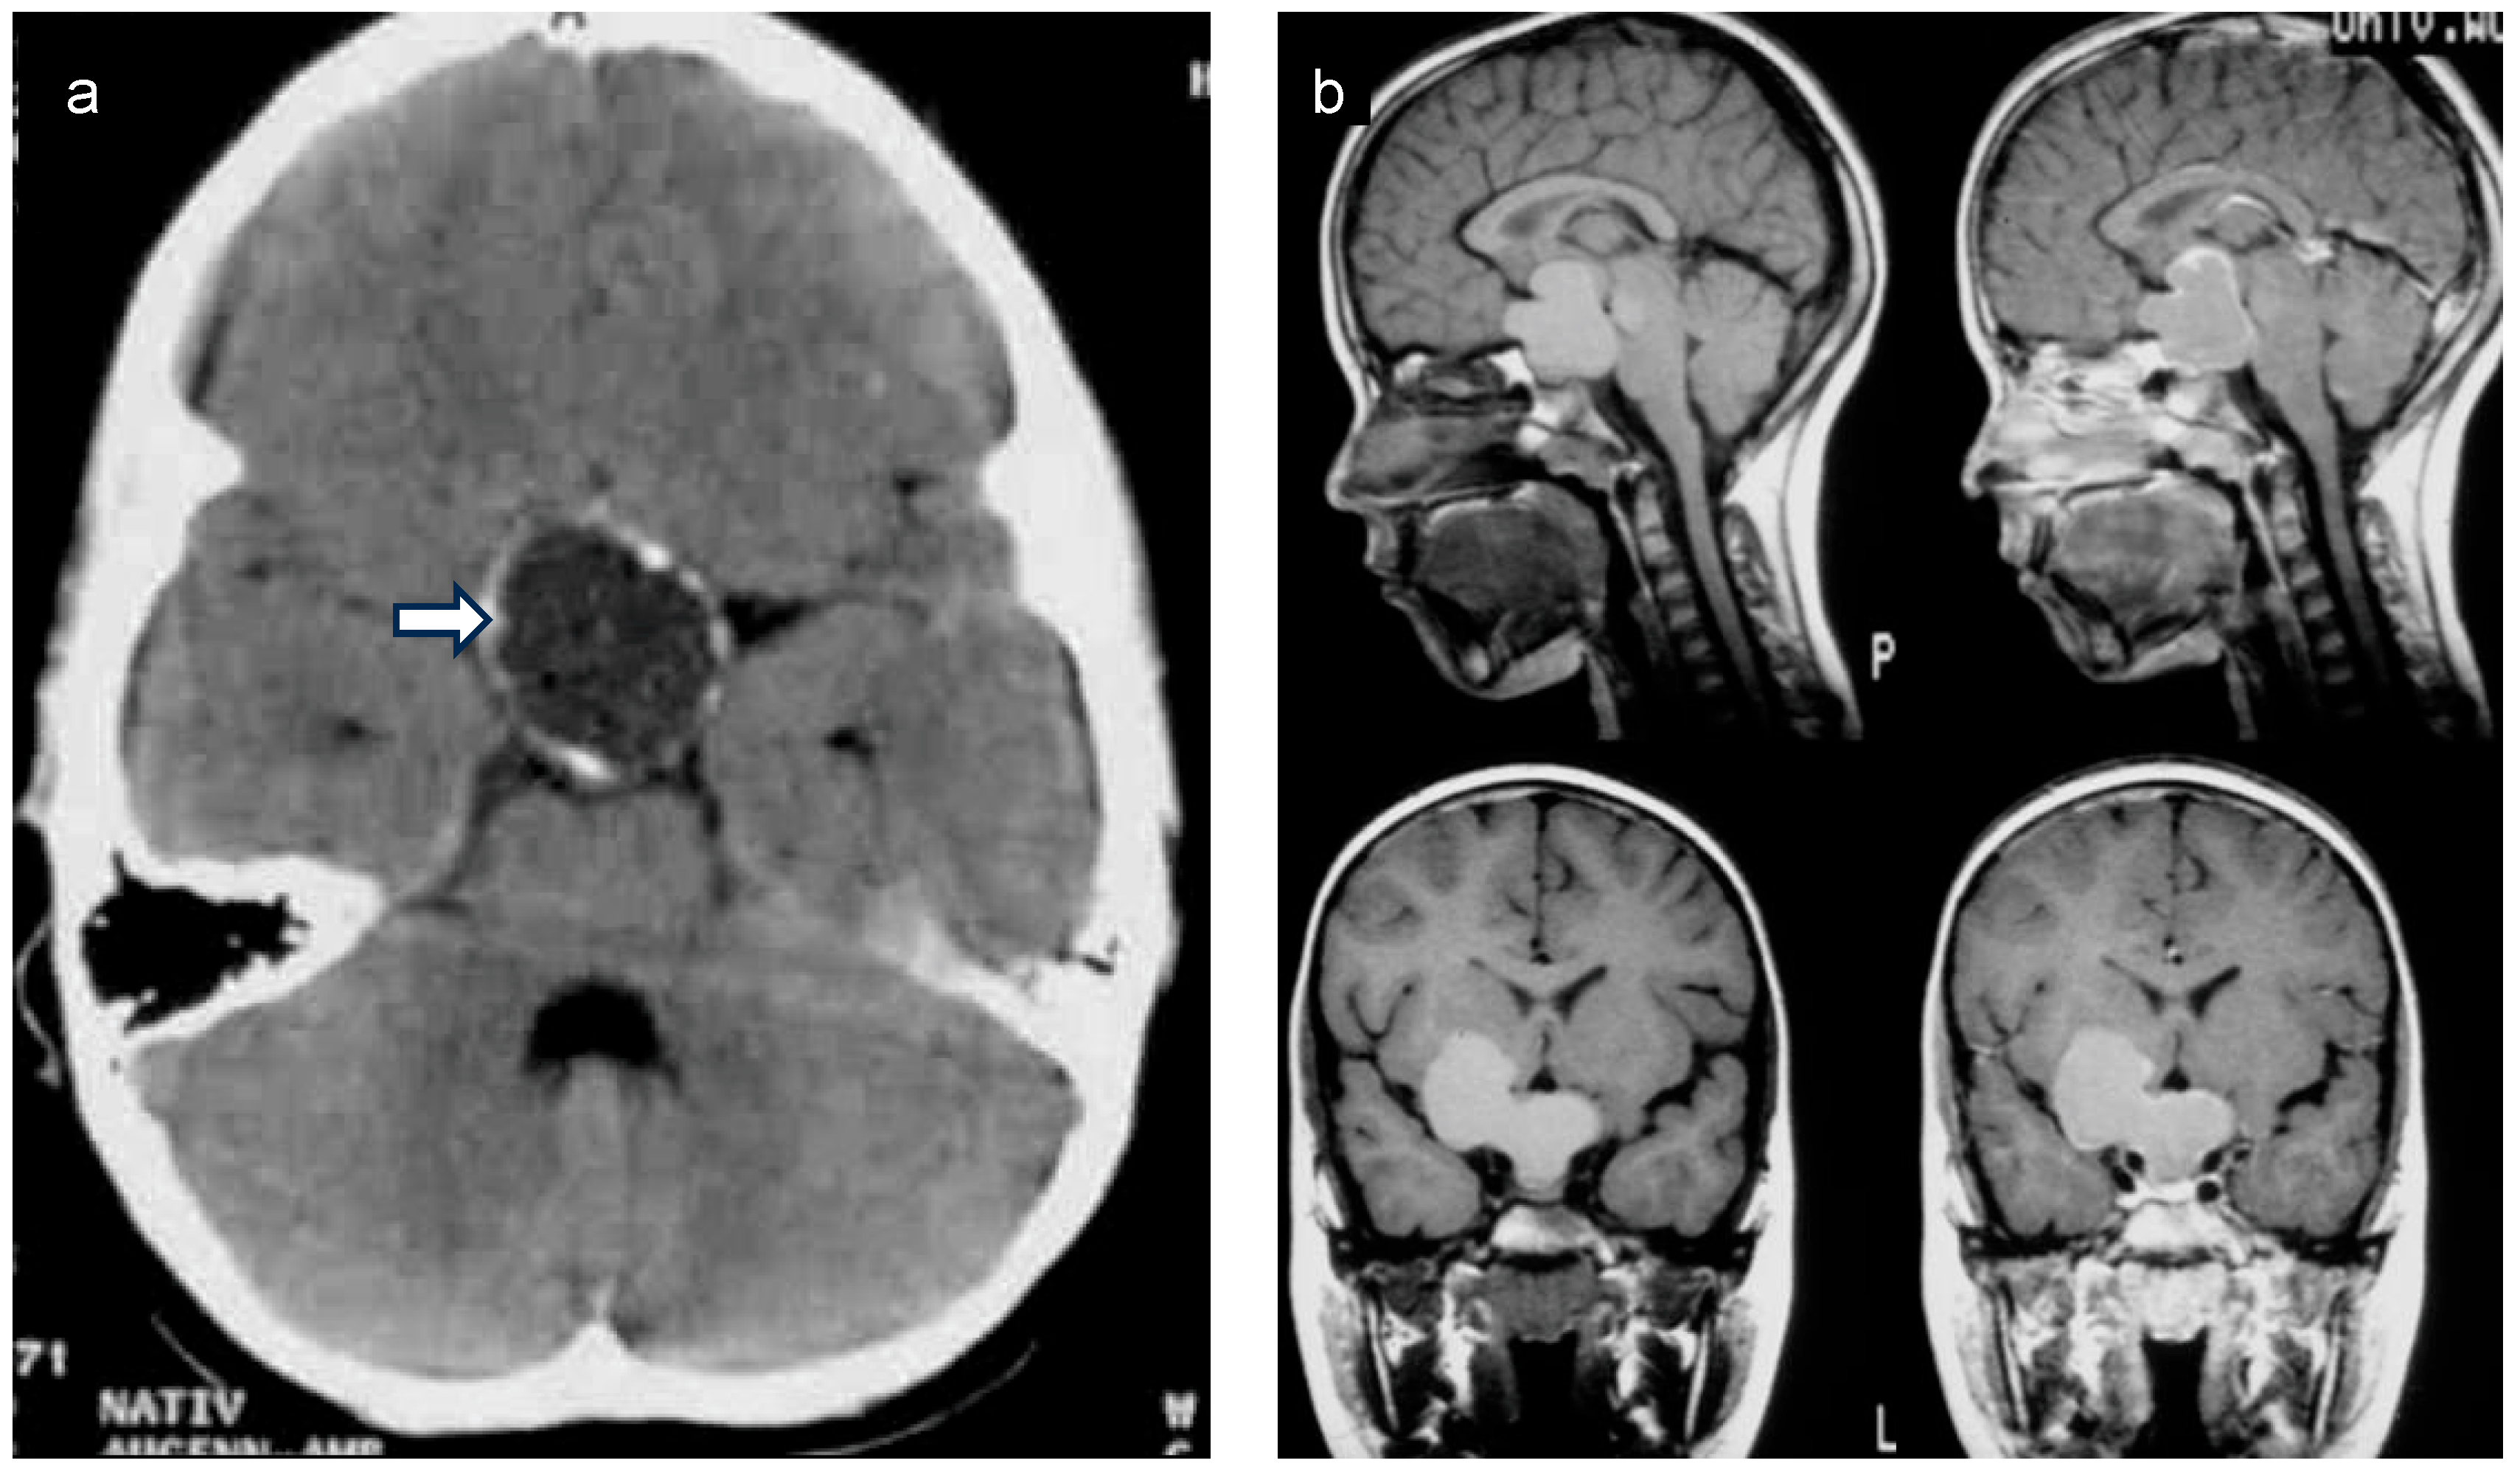

2. Anatomical Location of Childhood-Onset Craniopharyngioma Close to the Hypothalamus

3. Diagnosis, Treatment, and Follow-Up Care of Patients with Childhood-Onset Craniopharyngioma